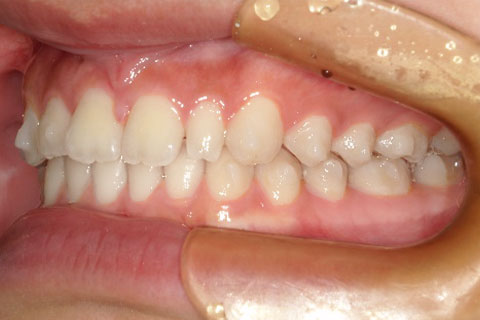

主訴:上下の歯並びのガタガタが気になる

診断名:上下顎叢生

症状:上下顎叢生

患者プロフィール:北九州市・小倉北区30代女性

治療方針:非抜歯治療

治療装置:マウスピース型矯正治療(インビザライン)

抜歯:無し

治療期間:一年半

通院回数:30回

リテーナー:上顎プレートタイプリテーナー 下顎フィクスタイプリテーナー

治療費用:検査診断料(20,000)+装置料金(500,000)+管理調整料(150,000) +装置撤去時診断料(10,000) +保定装置料金(20,000)=700,000(消費税込)

リスク副作用:痛み・治療後の後戻り・歯根吸収・歯髄壊死

詳しい症例説明:この患者さんはガタガタが気になり来院されました。マウスピースタイプの矯正装置で比較的短期間で治療を終えることができました。インビザライン(マウスピース矯正治療)で矯正治療を行うことで取り外して食事ができ、痛みもそれほど感じなかったとのことです。